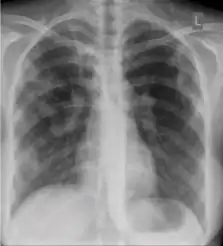

Normal findings

These are films that are completely normal, with no identifiable cardiothoracic or musculoskeletal abnormality.